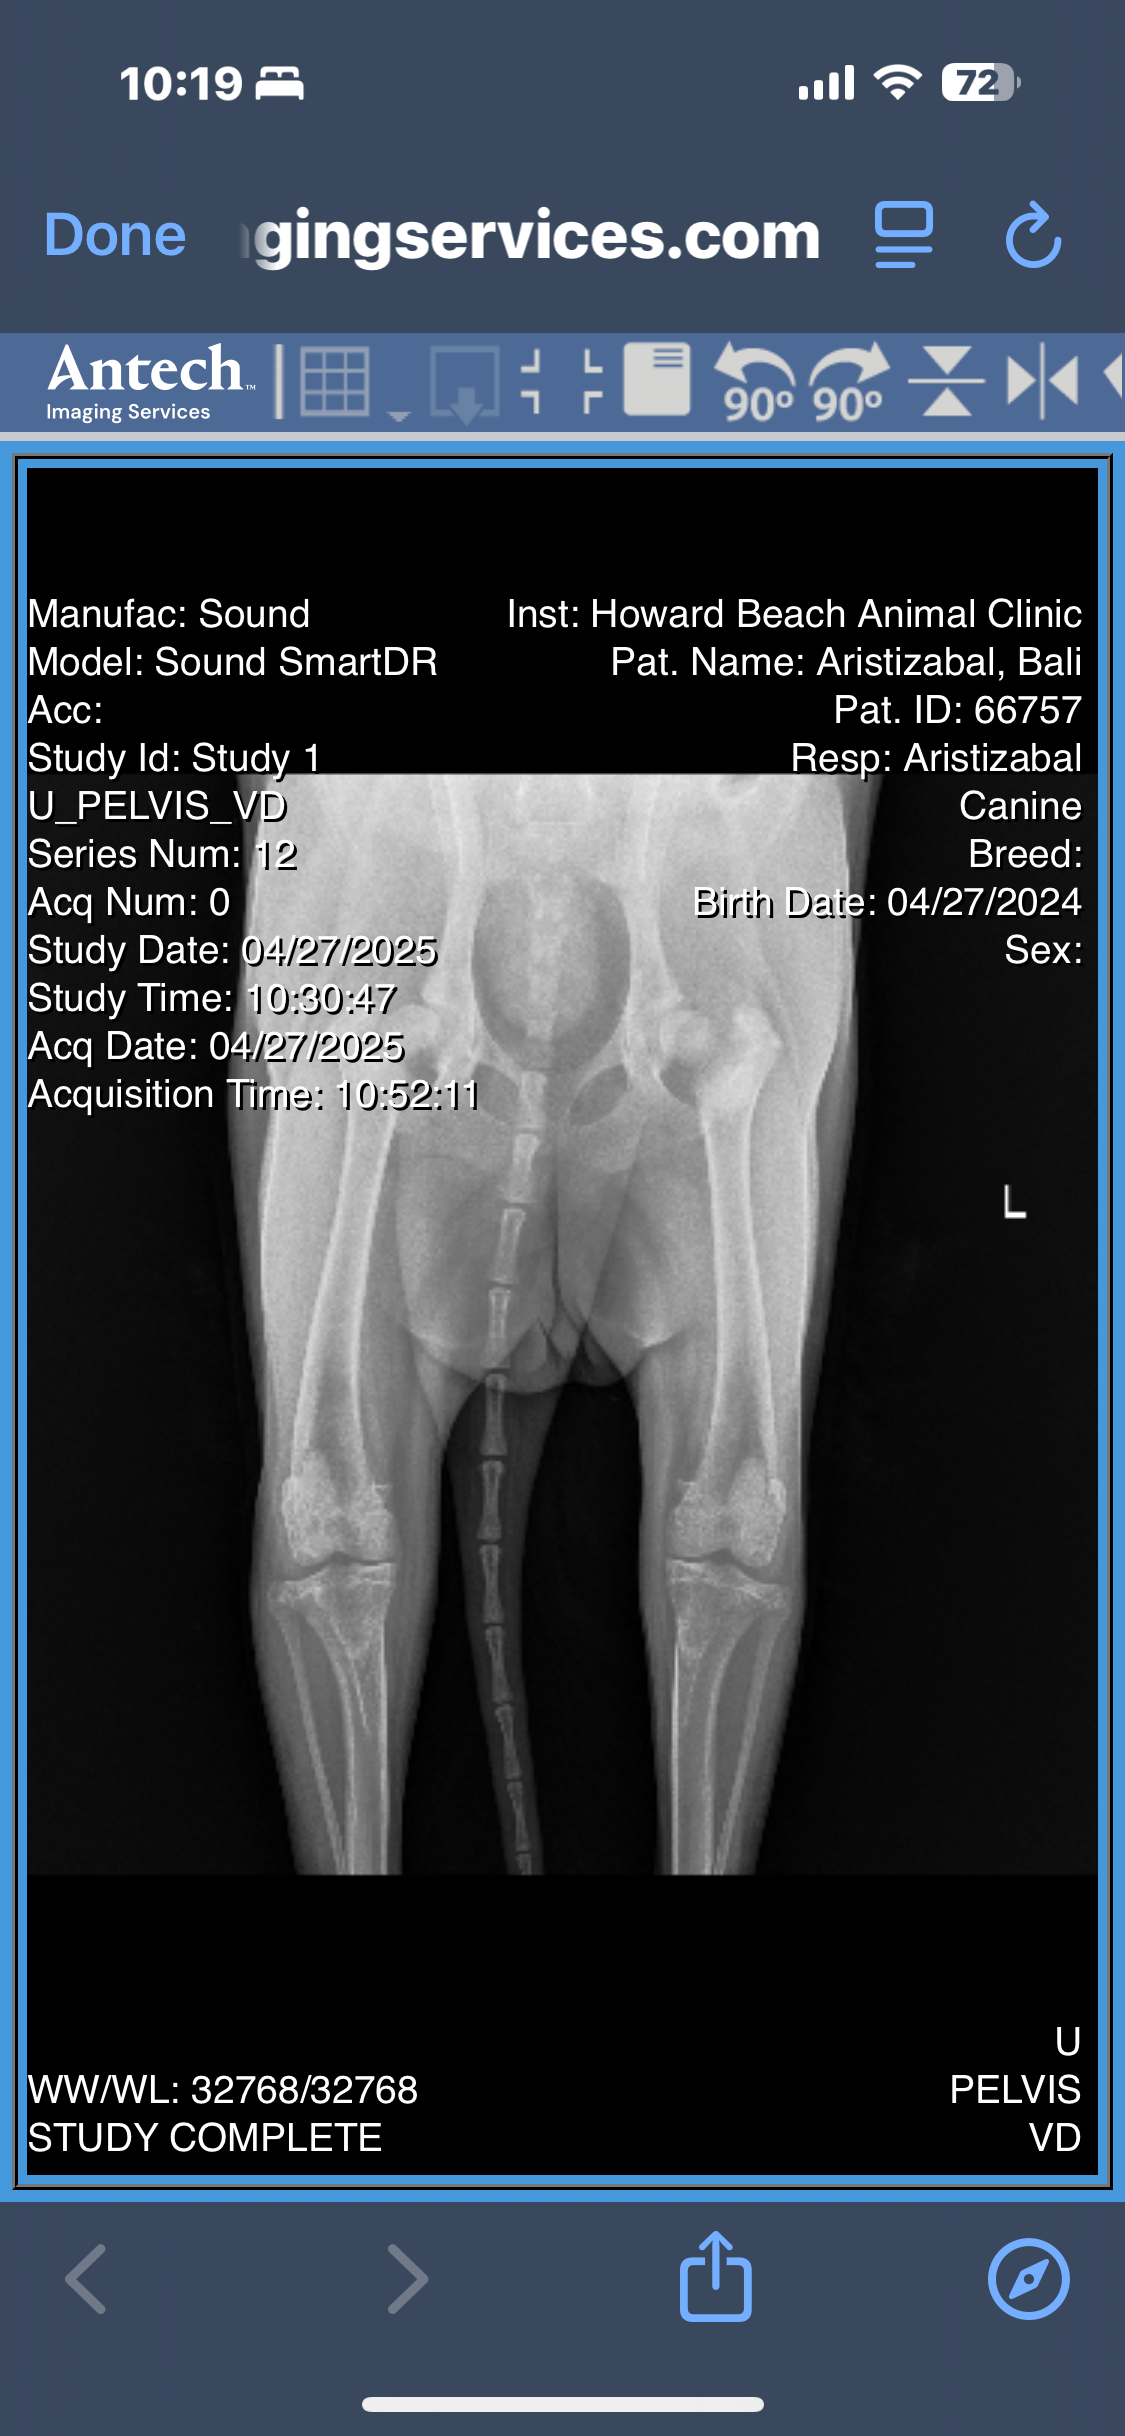

After months of limping, discomfort, and visits to the vet, Bali’s radiographs revealed multiple orthopedic issues:

• A minimally displaced fracture in her left femoral neck

• Severe bilateral hip dysplasia, more advanced on the left

• Osteoarthritis in both hips, with significant muscle atrophy

• Possible avascular necrosis of the femoral head or slipped femoral capital epiphysis

• And the concern of an underlying septic arthritis that hasn’t yet been ruled out